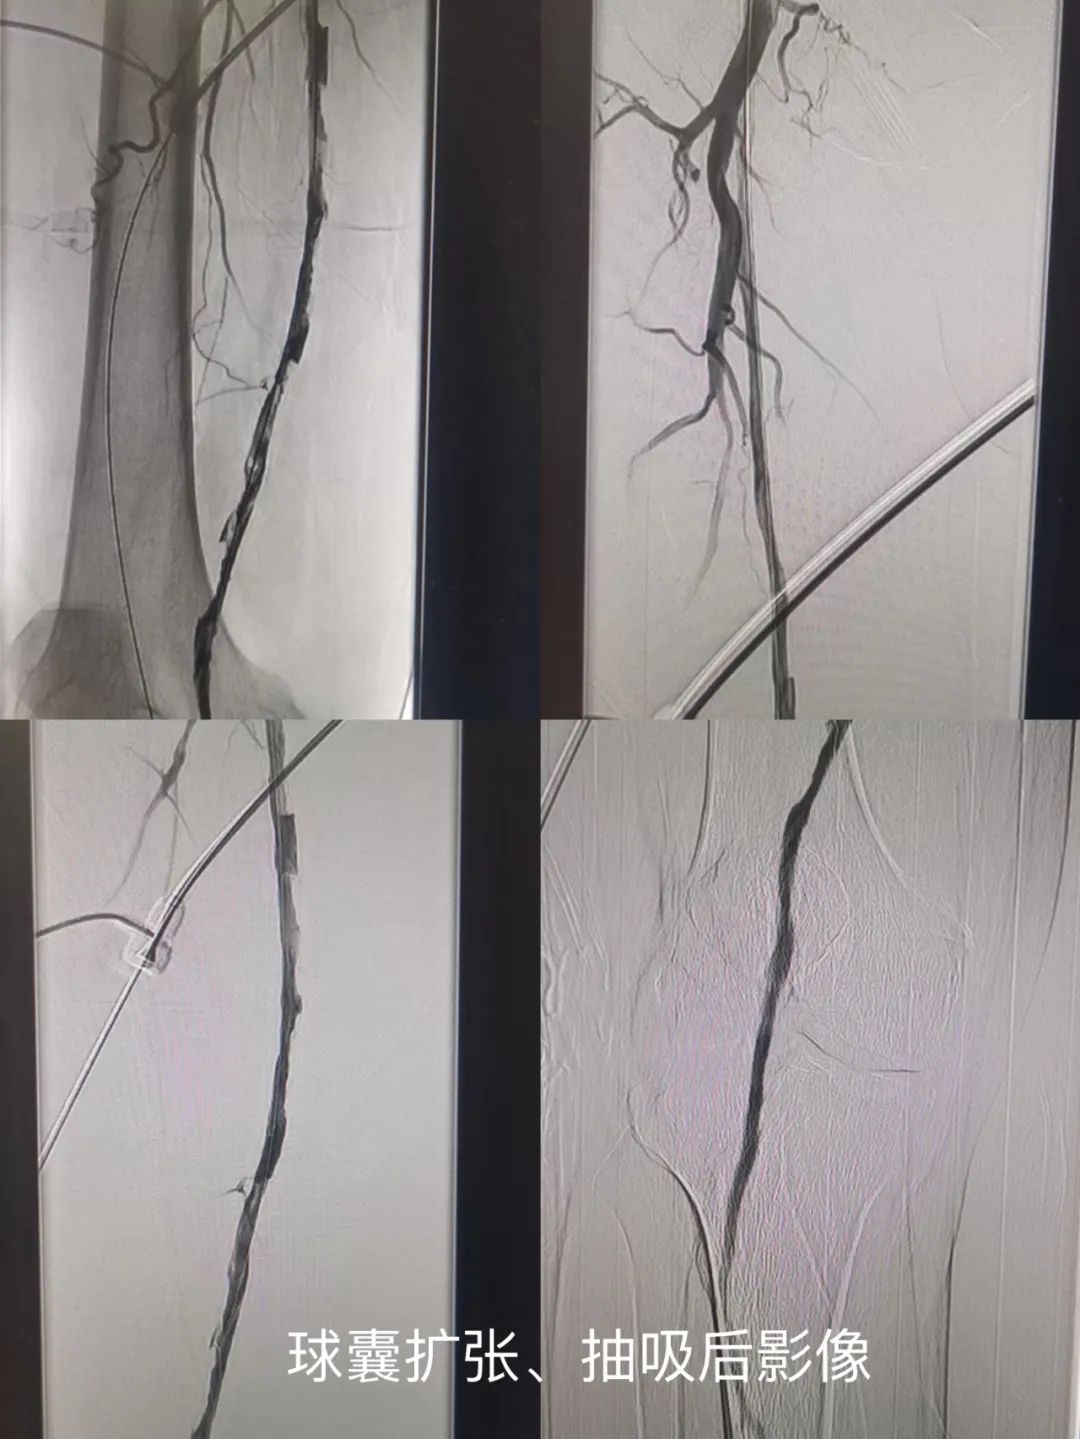

李某,男,81岁,因“右下肢疼痛10余天”入院,既往高血压病史50年,血压控制尚可。入院后行下肢动脉CTA提示右侧股浅动脉、腘动脉闭塞,给予抗凝、抗板治疗,仍有静息痛存在。面对患者高龄且病情重的情况,魏东升主任经术前讨论,考虑到患者为近期(14天以内)血栓形成,若不尽早恢复肢体血流,很容易导致下肢的缺血坏死,甚至可能面临截肢的风险,需尽早进行手术。经术前讨论后,预行下肢动脉球囊扩张、下肢动脉内血栓旋切术。应用Rotarex血栓抽吸减容系统,以40000转/分钟钻头将血栓切碎,同时将其抽吸出体外。术毕患者右下肢皮温良好,患者自觉症状明显缓解,此例手术过程中未植入支架,符合DCB血管治疗时代的“leave nothing behind”理念。可最大限度避免术后并发症的出现。经术后随访患者恢复良好,无间歇性跛行、无静息痛,症状明显缓解。